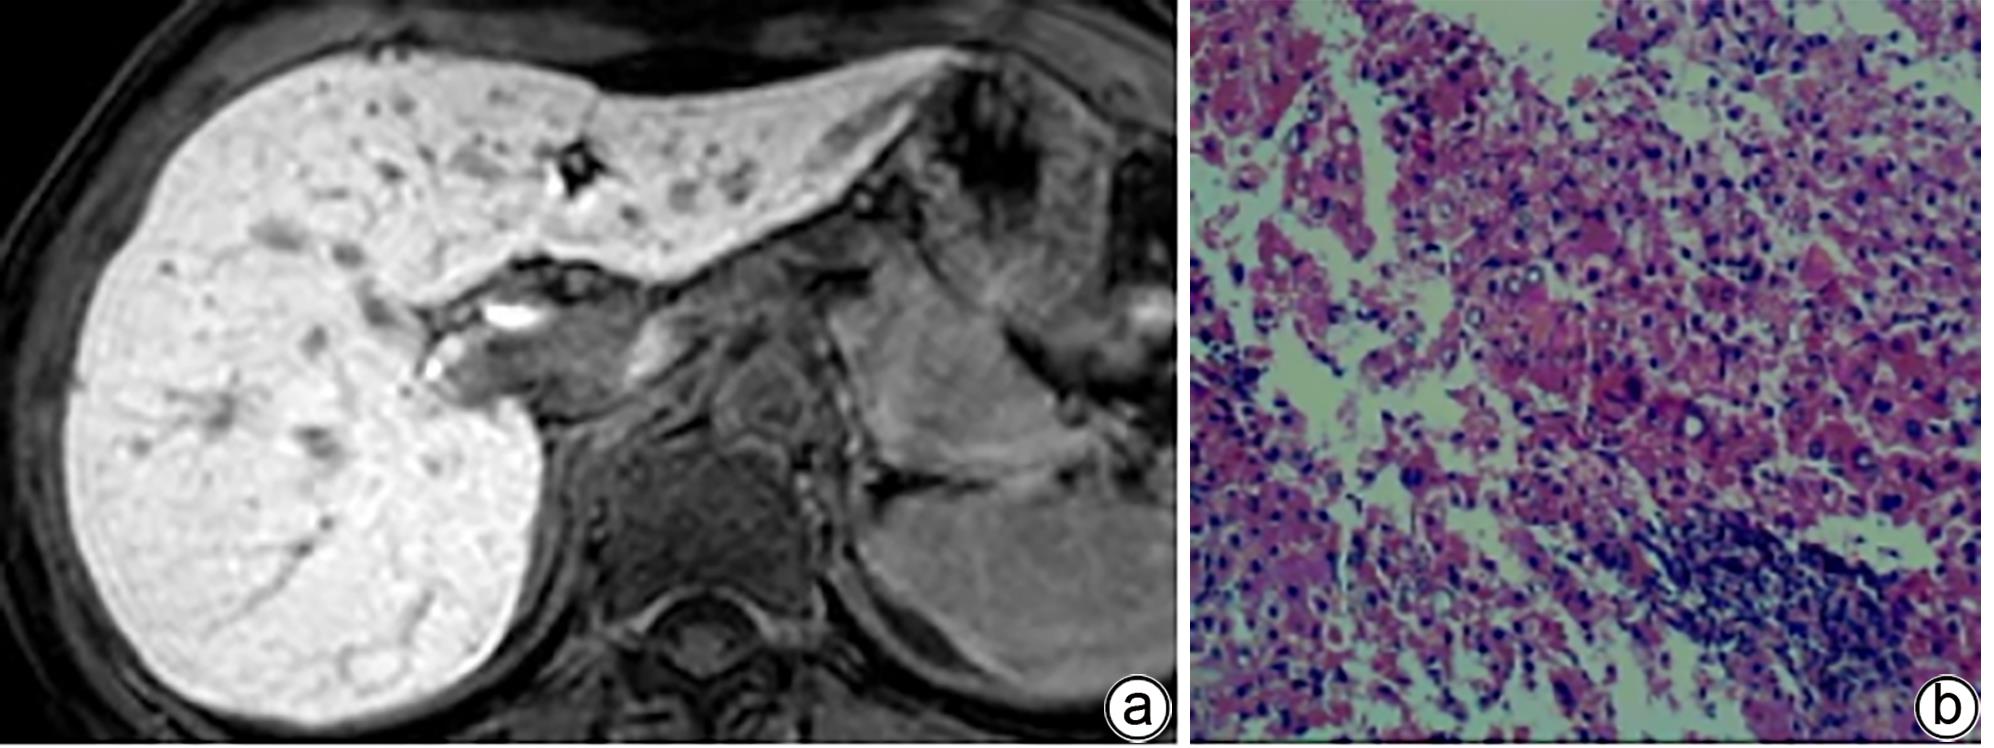

Value of MRI biliary score and liver/muscle ratio in evaluating the pathological grade of liver fibrosis

Lu HUANG, Lijian LU

2024, 40(4): 720-725. DOI: 10.12449/JCH240413

Abstract(1187) HTML (328) PDF (1168KB)(71)

Abstract:

Objective  To investigate the value of biliary score and hepatic signal intensity-to-muscle signal intensity ratio (HMR) obtained by multiphase contrast-enhanced MRI scan using Gd-EOB-DTPA in evaluating the pathological grade of liver fibrosis.  Methods  A retrospective analysis was performed for the MRI and clinical data of 51 patients with chronic hepatitis B liver fibrosis in Wuming Hospital Affiliated to Guangxi Medical University from January 2020 to May 2023. The 51 patients with liver fibrosis were divided into low-grade group (S1-S2) and high-grade group (S3-S4). GE Architact 3.0T MR scanner was used to perform MRI scans, including routine plain scan and contrast-enhanced scan at arterial phase, portal venous phase, delayed phase, hepatobiliary phase, and excretory phase, and biliary score and HMR were measured for the patients with different grades of liver fibrosis. The t-test was used for comparison of continuous data between groups, and the chi-square test or the Fisher’s exact test was used for comparison of categorical data between groups. The receiver operating characteristic (ROC) curve was plotted to evaluate the value of MRI indicators in determining the pathological grade of liver fibrosis.  Results  Among the 51 patients with liver fibrosis, there were 30 patients in the low-grade group and 21 in the high-grade group. Compared with the high-grade group, the low-grade group had significantly higher biliary score (3.67±0.55 vs 2.57±0.75, t=6.05, P<0.001) and HMR at portal venous phase (2.38±0.76 vs 1.97±0.18, t=2.41, P=0.020), delayed phase (2.48±0.70 vs 1.99±0.27, t=3.09, P=0.003), and hepatobiliary phase (4.10±0.63 vs 3.16±0.47, t=5.81, P<0.001). The above indicators had an area under the ROC curve (AUC) of 0.86, 0.79, 0.82, and 0.88, respectively, in distinguishing low- and high-grade liver fibrosis, with a positive rate of 70%, 63.3%, 83.3%, and 96.7%, respectively, and a negative rate of 90%, 95.2%, 74.1%, and 100%, respectively, in the diagnosis of high-grade liver fibrosis. Biliary score combined HMR had an AUC of 0.95, with a positive rate of 85.7% and a negative rate of 96.7%.  Conclusion  Biliary score and HMR at hepatobiliary phase obtained by multiphase contrast-enhanced MRI scan using Gd-EOB-DTPA has a relatively high diagnostic efficacy in distinguishing between low- and high-grade liver fibrosis and a certain guiding value for the diagnosis and treatment of liver fibrosis in clinical practice.